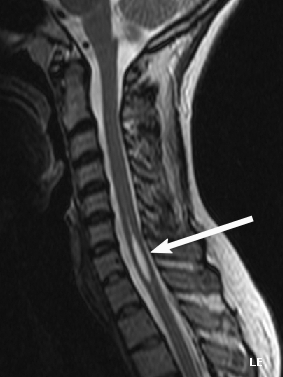

- Chụp cộng hưởng từ (MRI): Là tiêu chuẩn vàng để chẩn đoán.

- Chuỗi xung T1-weighted: Syrinx thường giảm tín hiệu.

- Chuỗi xung T2-weighted: Syrinx tăng tín hiệu rõ rệt, cho thấy hình ảnh khoang chứa dịch.

- Tiêm thuốc đối quang từ (Gadolinium): Giúp xác định các nguyên nhân kèm theo như khối u, viêm nhiễm.

- MRI Cine flow: Có thể đánh giá động lực học dòng chảy CSF ở ngã ba sọ-cổ, đặc biệt hữu ích trong trường hợp nghi ngờ dị tật Chiari.